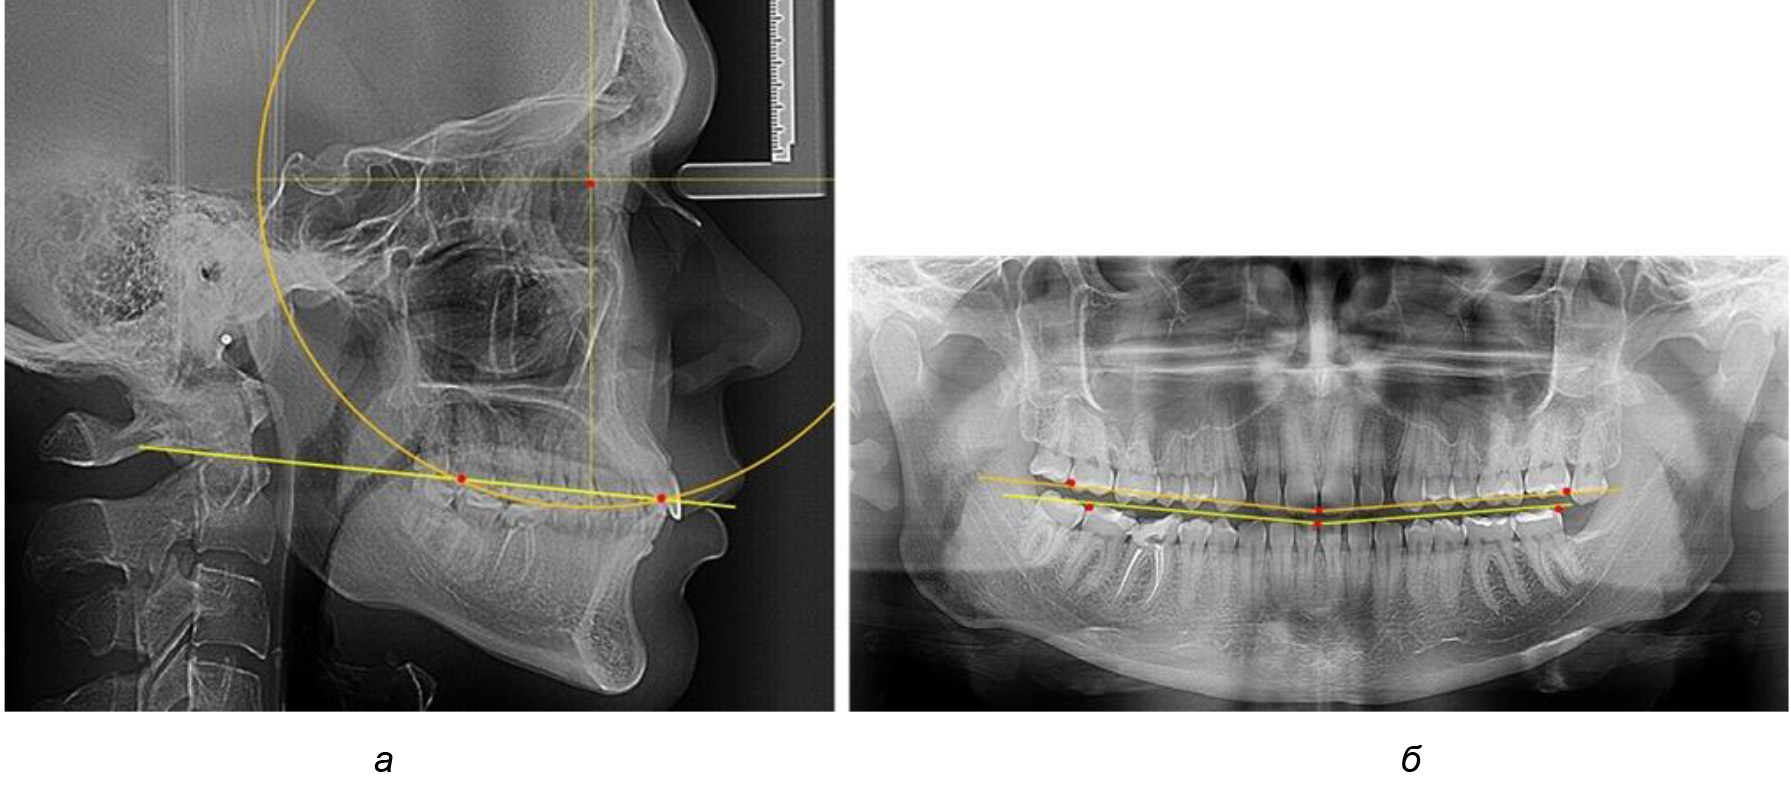

В 3-ю подгруппу вошли ТРГ и ОПТГ 14 человек 1-й группы, что составило (22,58 ± 5,31) % от общего количества людей 1-й группы. Величина угла нижней челюсти в среднем составила (114,85 ± 2,87)° и характеризовала горизонтальный тип нижней челюсти.

Глубина кривой Spee в среднем по 2-й подгруппе составил (2,94 ± 0,47) мм, что было меньше, чем в других подгруппах. Деление величины радиуса круга к длине окклюзионной линии составило 1,616 ± 0,02 (рис. 4).

Рис. 3. Особенности кривой Spee на ТРГ (а) и ОПТГ (б) при нейтральном типе роста нижней челюсти

Рис. 4. Особенности кривой Spee на ТРГ (а) и ОПТГ (б) у людей с горизонтальным типом лица